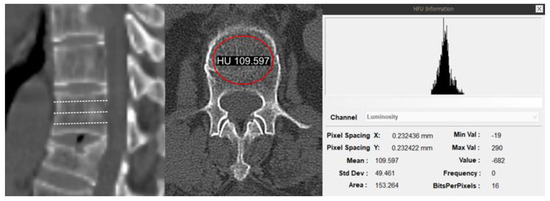

2.5. Radiological Assessment